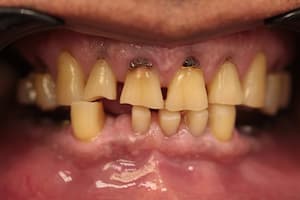

До

После

Удаление 7 зубов, установка 11 имплантов Straumann, временное и постоянное протезирование всех зубов с учетом формы, цвета и размера зубов. Работа с мягкими тканями. Импланты использовались для немедленной нагрузки.